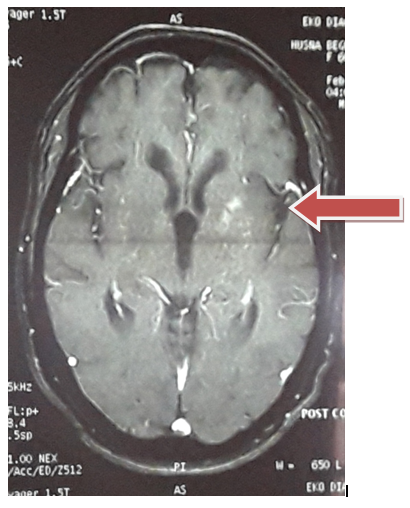

Figure 1 Generalised cerebral and cerebella atrophic changes are seen with ischemic leukoaraiosis. Left putaminal region is showing signal changes? metabolic in nature. Hyperintense lesion left basal ganglia region. Absence of other metabolic abnormalities & systemic processes like lupus, hyperthyroidism and uremia apart from uncontrolled DM. No History suggestive of Rheumatic fever. Plus, resolution of her movement disorder with control of hyperglycemia; led us to conclusion that-Chorea was likely due to uncontrolled hyperglycemia.

Figure 1 MRI Brain showing lesion in left basal ganglia.